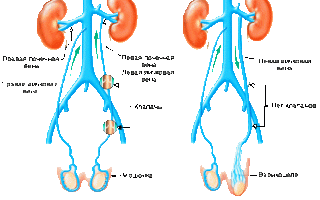

Сравнение здоровых и пораженных заболеванием яичек

Варикоз вен семенного канатика чаще всего развивается слева. Это связано с тем, что семенная вена может впадать в почечную под прямым углом. Она длиннее, чем аналогичные сосуды, что приводит к повышенному давлению в ней. Таким образом, семенная вена становится более уязвимой и чаще подвергается варикоцеле.

Аорто-мезентериальный «пинцет», образованный верхней брыжеечной артерией и стволом аорты, может защемлять левую почечную вену, что приводит к венозному рефлюксу – обратному току крови в левую яичковую вену. В результате этого гроздевидное сплетение в семенном канатике переполняется кровью.

Правостороннее и даже двустороннее варикоцеле также встречаются, но значительно реже.

сравнение здоровых яичек и с варикоцели